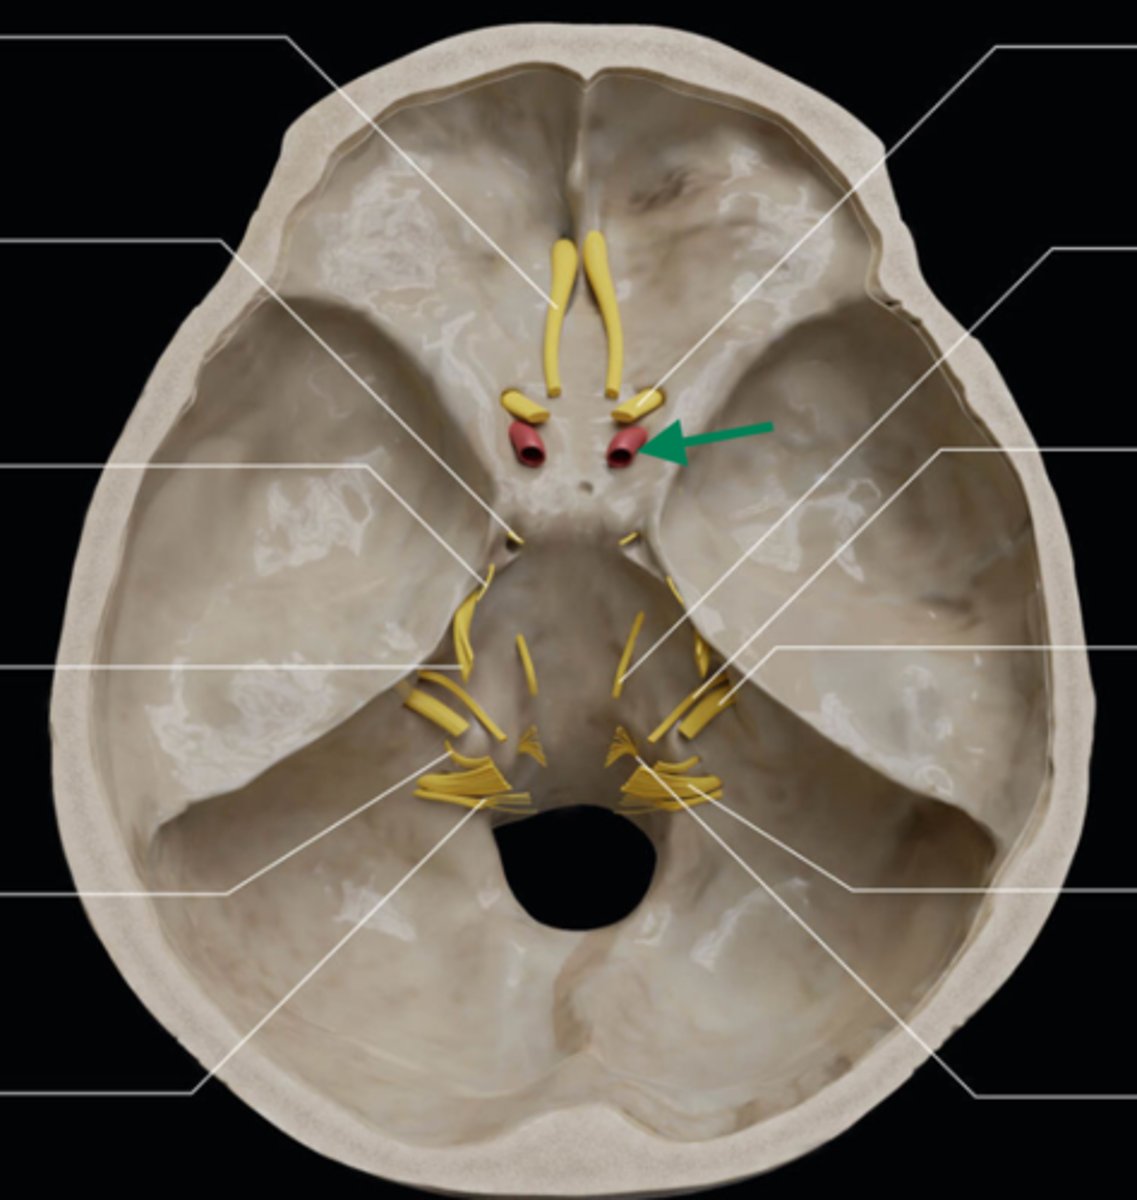

olfactory bulb

olfactory tract

optic nerve (CN II)

internal carotid artery

oculomotor nerve (CN III)

trochlear nerve (CN IV)

abducent nerve (CN VI)

trigeminal nerve (CN V)

facial nerve (CN VII)

vestibulocochlear nerve (CN VIII)

glossopharyngeal nerve (CN IX)

vagus nerve (CN X)

accessory nerve (CN XI)

hypoglossal nerve (CN XII)

optic chiasm

trigeminal ganglion

anterior cranial fossa